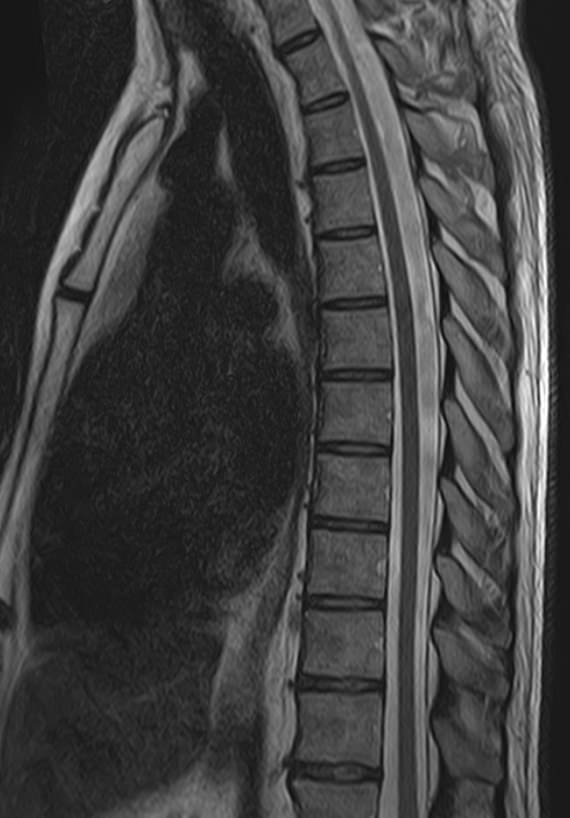

Магнитно-резонансная томография является наиболее чувствительным и эффективным методом диагностики дегенеративно-дистрофических заболеваний, травматических, воспалительных изменений, а также опухолевых процессов позвоночника. Метод позволяет оценить состояние структур позвонков, позвоночного канала с расположенным в нем спинным мозгом и окружающих мягких тканей, кроме того является основным способом диагностики демиелинизирующих заболеваний спинного мозга.

В клинике Доступная медицина установлен новейший высокопольный томограф экспертного класса TOSHIBA VANTAGE TITAN 1,5 Тесла, на котором выполняется комплексное обследование позвоночника. За счет высокой напряженности магнитного поля аппарат при сканировании создает изображения на плоскости превосходной четкости, затем с помощью компьютерных приложений данные преобразуются в изображения трехмерного формата, что обеспечивает точность и достоверность диагностики.

При подозрении на распространенный процесс с поражением различных уровней позвоночника в клинике «Доступная медицина» возможно проведение комплексной МРТ позвоночника – 3 отдела.